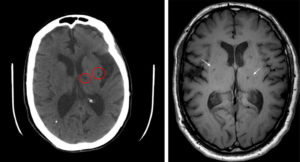

УЗ — диагностика с допплерографией выявляет нарушения в сосудах головного мозга (асимметрия, повышение венозного тока крови, стеноз, атеросклероз). КТ (компьютерная томография), определяет перенесенные инфаркты, скопление жидкости в полостях и истончение тканей (атрофия мозговых структур).

Наиболее достоверные и точные результаты возможны, получить только при исследовании с помощью магнитно — резонансной томографии (МРТ) черепа. Изображение получают путем взаимодействия электромагнитного поля с атомами водорода.

Данная диагностика позволяет оценить функционирование нейронов и обнаружить изменение плотности тканей мозга. Выявив бессимптомные стадии очагового поражения, возможно, начать своевременную терапию.

МРТ позволяет получить снимки в трех плоскостях (поперечная, продольная и фронтальная) и выявить причину нарушения питания мозговых структур:

Выявленная патология при помощи МРТ, позволяет оценить скорость прогрессирования заболевания и выбрать правильную тактику лечения.

Магнитная резонансная томография является одним из самых используемых методов в выявлении нарушений циркуляции крови головного мозга. Благодаря трехмерному изображению специалист может проанализировать все протекающие процессы и увидеть нарушения или новообразования.

Метод МРТ используется в первую очередь для диагностики. Применяются так же неврологические исследования и УЗИ тканей мозга.

Чтобы выявить патологические изменения, происходящие в ГМ, проводят магнитно-резонансную томографию.

Это единственный метод узнать, что именно происходит под черепной коробкой, увидеть все неблагоприятные процессы в структуре мозга, оценить возможные последствия и сделать максимально точный прогноз развития недуга.

В диагностике очаговых поражений головного мозга МРТ – «золотой» метод, способный дать наиболее точную оценку болезни. Он является не инвазивным, быстрым и высокоинформативным.

МРТ позволяет определить наличие очага поражения, а также провести сравнительный анализ полученных снимков со снимками здорового мозга. На них практически все очаги выглядят как светлые пятна различных размеров.

Помимо этого, магнитно-резонансная томография помогает точно установить количество очагов. Единичные изменения в головном мозге наблюдаются у всех пациентов в возрасте старше 50 лет. В подобных случаях необходимо следить за динамикой развития очага, а также принимать меры по ликвидации причин поражения ГМ.

При необходимости провести исследования кровеносных сосудов назначают МРТ с контрастом. В результате введения контрастного вещества кровь окрашивается в другой цвет, что отражается особыми оттенками на снимках МРТ. При их анализе врач видит, как течет кровь по сосудам, в каких направлениях и есть ли повреждения, тромбы, аневризмы.